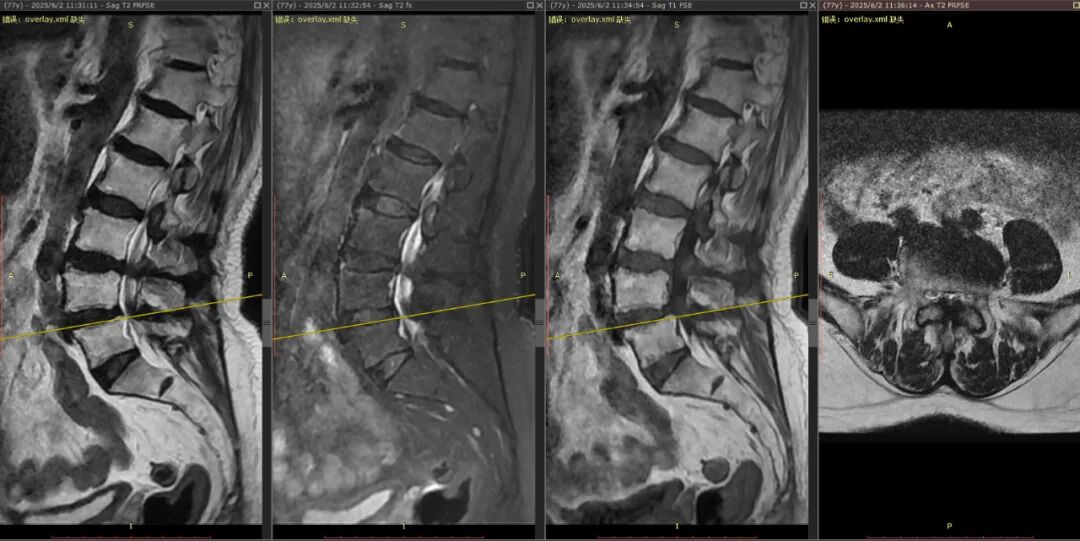

接診后,周大爺?shù)暮舜殴舱窠Y(jié)果讓醫(yī)生們也倒吸一口涼氣:他的兩節(jié)腰椎管已極度狹窄,神經(jīng)結(jié)構(gòu)幾乎被擠壓到無法分辨,手術(shù)難度和風(fēng)險極大。

周大爺?shù)暮舜殴舱窠Y(jié)果。

“對于僅有腰痛的患者,我們通常不輕易推薦手術(shù),需要下肢癥狀作為指征。但考慮到周大爺?shù)耐纯喑潭群蛷娏业闹委熞庠?,加上家屬的無比信任,讓我們決定為他實施目前最先進(jìn)的微創(chuàng)手術(shù)?!痹≤娭魅握f。

經(jīng)過周密評估,曾小軍團(tuán)隊為周大爺量身定制了“椎間孔鏡下單側(cè)入路雙側(cè)減壓+骨水泥強化椎弓根釘內(nèi)固定”的手術(shù)方案。曾主任通俗地解釋道:“這好比一條被淤泥堵塞的河道。我們只需通過一側(cè)一個不足1厘米的切口,就能在內(nèi)鏡的輔助下,為雙側(cè)受壓的神經(jīng)‘清淤拓寬’,精準(zhǔn)解除壓迫。同時,用骨水泥加固螺釘,就像給老化的骨骼‘焊接鋼筋’,確保脊柱在減壓后依然穩(wěn)固?!?/p>